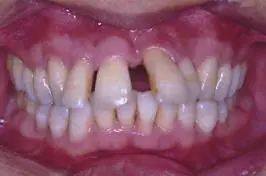

3、牙齒前突:當(dāng)前牙的傾斜度不良,無論是外突,還是向內(nèi)傾斜,都會(huì)影響到牙齒和面部的美觀。如圖3所示的上牙前突,上下前牙之間咬合距離大,專業(yè)術(shù)語就是深覆蓋。如圖3所示.

3,上前牙外突,唇向傾斜,上下牙之間咬合距離大